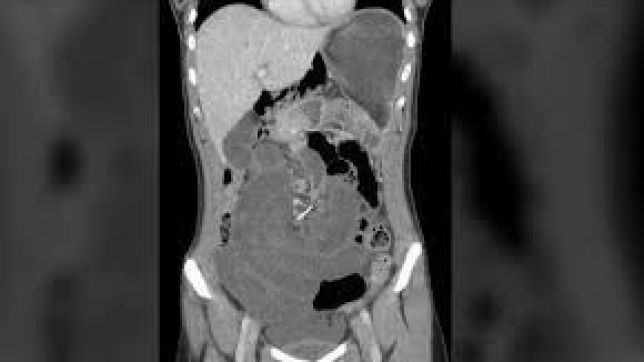

Uma tomografia revelou a presença de um fio de metal e mostrou que o objeto já havia atingido vários pontos do órgão. Devido às perfurações, o intestino estava revirado, causando um quadro clínico chamado vólvulo gástrico, caracterizado pela movimentação do órgão ao girar em torno do seu próprio eixo.

Considerando as constantes dores da mulher, a equipe médica resolver realizar um procedimento cirúrgico de emergência. Ao final, o fio metálico, de sete centímetros, foi retirado. Para Talia Shepherd, uma das médicas responsáveis pelo caso, acidentes desse tipo são muito raros e incomuns.